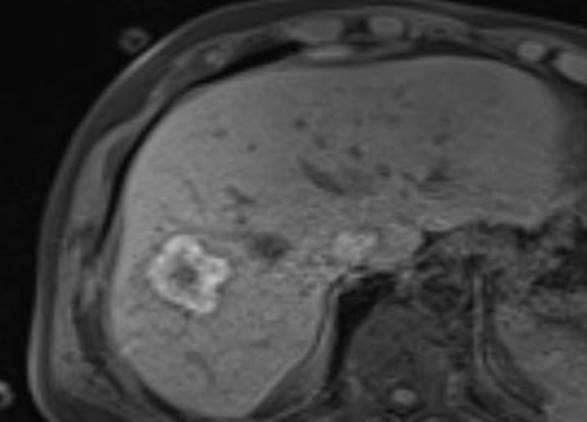

Die minimalinvasive Thermoablation ist eine Therapieoption für Leberkarzinome und Lebermetastasen. Voraussetzung hierfür ist, dass bestimmte Bedingungen wie Tumorgröße, Anzahl und Lage des Zieltumors erfüllt sein. Ob ein Lebertumor mit einem thermoablativen Verfahren (Mikrowellenablation oder Radiofrequenzablation) sicher und effektiv behandelt werden kann, wird vor der Therapie interdisziplinär mit Kollegen aller für diese Fragestellung relevanter Fachrichtungen besprochen.

Bei der perkutanen Thermoablation von Nierentumoren werden spezielle Applikatoren unter CT- oder MRT Bildgebung in den Zieltumor eingebracht. Durch Hitze wird der Tumor zerstört.